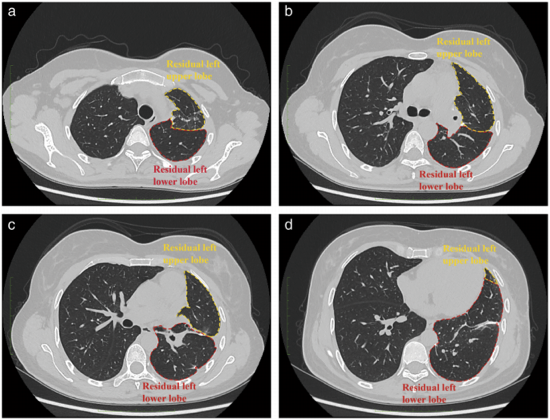

术后5天拔除胸管,患者顺利康复,次日出院。术后3个月进行HRCT检查,证实患者的左肺没有残余结节,残余肺扩张良好(图2)。术后随访2年,无复发迹象。

图2. 术后3个月胸部高分辨率CT扫描显示,患者左肺保存完好,无结节残留,残留左肺扩张良好